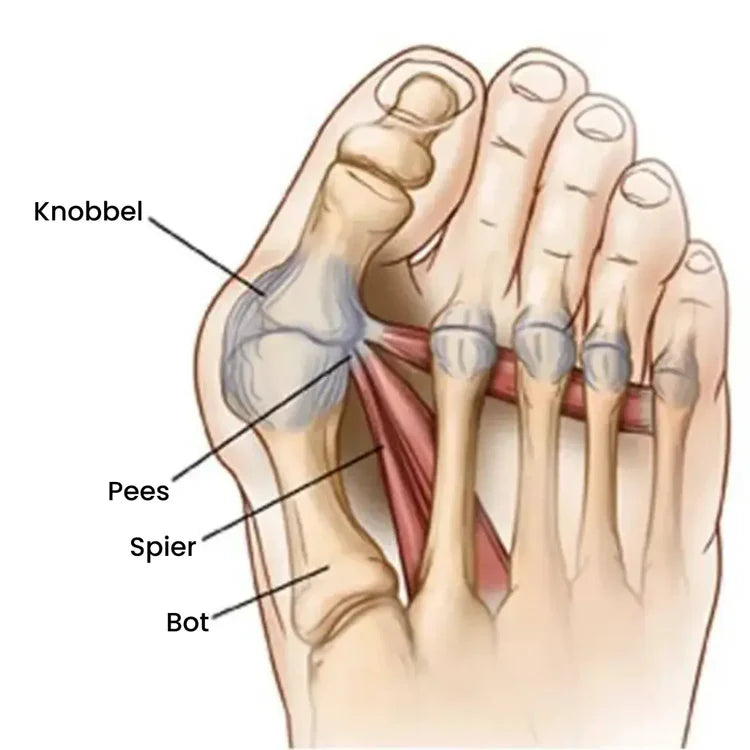

Die pijnlijke bult is niet zomaar "extra bot" dat chirurgisch verwijderd moet worden.

Wat er echt gebeurt is dat je grote teen ver uit zijn positie buigt.

De natuurlijke positie zou recht moeten zijn, net zoals de voeten van baby's eruitzien wanneer ze geboren worden.

De Echte Oorzaak: Spieronbalans

Strakke, smalle schoenen persen je tenen in onnatuurlijke houdingen, waardoor essentiële voetspieren verzwakken.

Door deze onbalans drijft je grote teen steeds verder naar binnen en steekt het gewricht naar buiten uit.